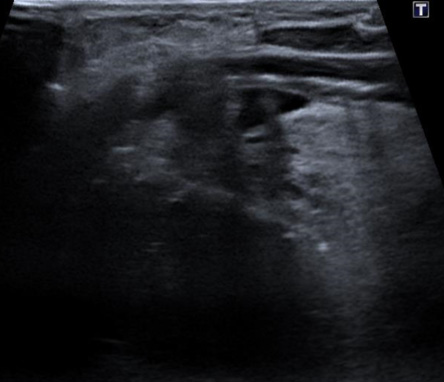

Introduction de l'électrode de radiofréquence dans le nodule sous guidage échographique en temps réel

La radiofréquence (RF) est une technique d'ablation thermique qui utilise des ondes électromagnétiques pour chauffer et détruire le tissu nodulaire depuis l'intérieur, sous guidage échographique en temps réel. Une fine électrode est introduite dans le nodule à traiter. Aucune cicatrice, aucune anesthésie générale.